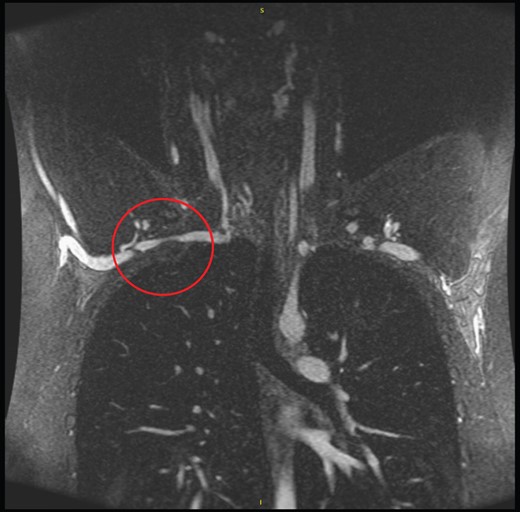

MRA of the chest showed a nonunion fracture of the right first rib with a large hypertrophic callus adjacent to the brachial plexus compressing the subclavian artery mildly (Fig. 1). No cervical rib was present. With radiographic evidence suggesting TOS, surgical decompression was offered to the patient. After discussion, the decision was made to proceed with transaxillary first rib resection.

Initial conservative management with injection and rehab for suspect labral tear was certainly congruent with conservative therapy for nTOS [1], but unfortunately provided only transient relief with continued athletic limitation. Therefore, with an obvious source for compression radiographically confirmed, and reproducible symptoms with provocative maneuvers, we felt surgical decompression with first rib resection and scalenectomy was reasonable. As with previously reported cases [4], we elected for a transbrachial approach as this allowed abundant exposure and access to the first rib and scalenes as well as visualization and protection of the neurovascular structures (Fig. 1).